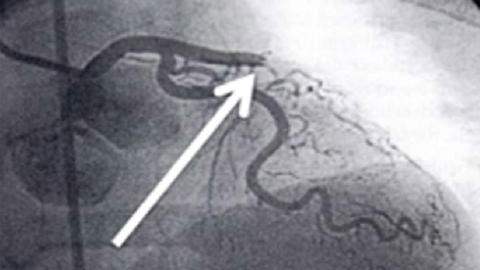

Verschlossenes Herzkranzgefäß

© herzmedizin.berlin Von einem Herzinfarkt spricht man, wenn ein Herzkranzgefäß nicht nur eingeengt, sondern komplett verschlossen ist.